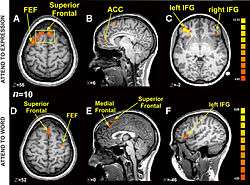

Research using functional magnetic resonance imaging of the brain suggests that cognitive and affective-expressive forms of communication and self-reflection have distinct neural bases.[50] Clinical findings have long suggested that verbalizations are often very incoherent when the individual is trying to put into words something deeply emotional.[51] Identification of words naming emotions (happy, neutral, sad) was found to be faster than identification of corresponding facial expressions. Recognition of face expressions was more difficult to suppress in favor of the recognition of words than vice versa, the two conditions presenting different patterns of brain activation. These experimental results suggest that reading and recognition of face expressions are stimulus-dependent and perhaps hierarchical behaviors, hence recruiting distinct regions of the medial prefrontal cortex.[48]

- 1 2 Ovaysikia S, Tahir KA, Chan JL, DeSouza JF (January 2011). "Word wins over face: emotional Stroop effect activates the frontal cortical network". Front. Hum. Neurosci. 4: 234. doi:10.3389/fnhum.2010.00234. PMC 3020489